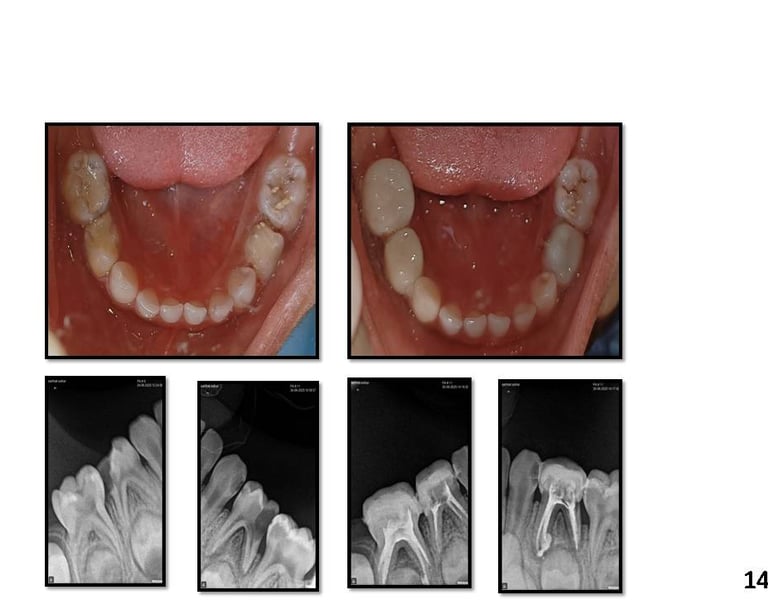

Cases

A new era of Pedocrown